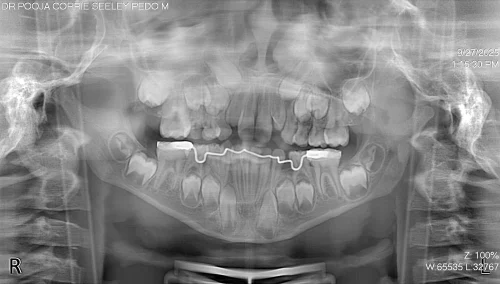

The complete clinical and radiographic evaluation, to include Orthopantomogram (OPG), exposed severe crowding of the lower anterior area, as well as premature loss of the lower left primary molar (#L), which leads to loss of space and causes the permanent teeth to migrate mesially. This diagnosis was sufficiently clear enough to result in the insertion of a fixed lingual holding arch with U loops to ensure space and support the symmetry of the arch until a natural eruption of successors.

The lingual holding arch was cemented with glass ionomer cement, which is adhesive and releases fluoride, as this gave an opportunity to expand the U-loops and adapt them to the lingual tooth surfaces. The process was done with a lot of care using a rubber dam to keep everything clean, and special tools were used to ensure the appliances were placed correctly.

The total chair time was approximately 30 minutes, distributed over two visits, one for scanning and the other for placement and adjustment. Post-placement, the child’s bite and comfort were carefully assessed, and oral hygiene instructions were delivered.